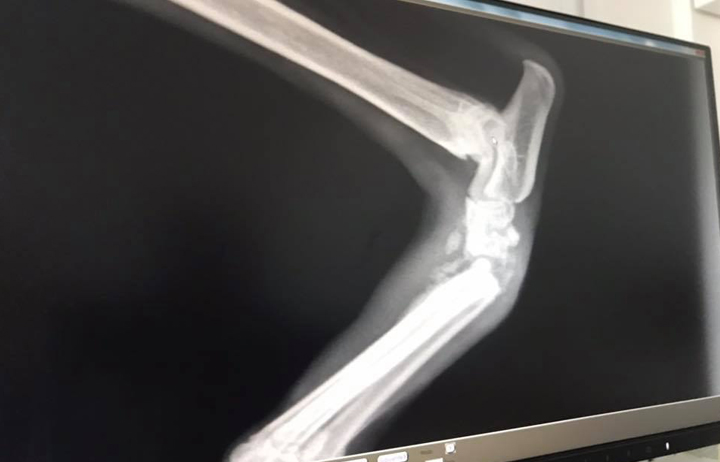

Sota was rescued from the streets will a terrible leg injury. This pretty girl is a sweetheart and will need an operation once her foot is in a better condition to heal. The toe isn’t even attached anymore, she’s very swollen, sore and in pain. More info to come.